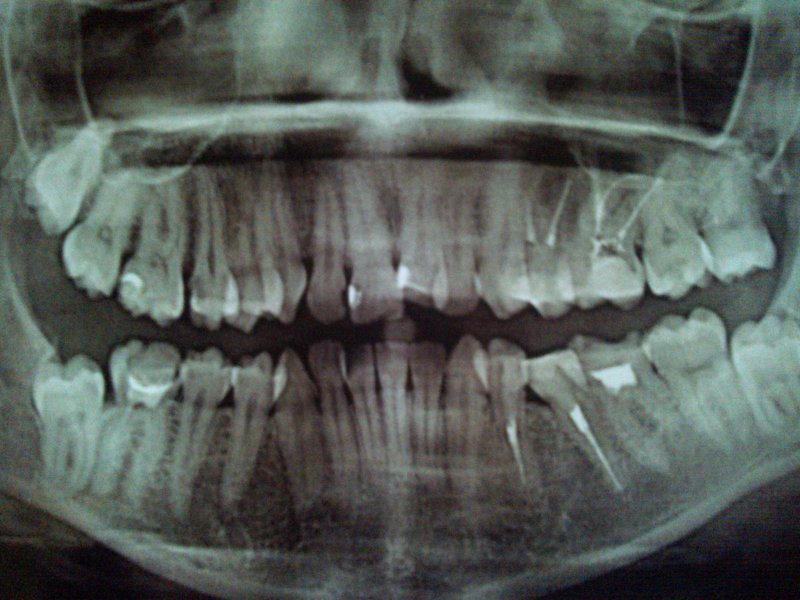

решила поставить брекеты, врач-ортодонт сказал удалять две верхних четвёрки. прав ли он или можно обойтись без удаления? |

юляяяяяя, здравствуйте.

По снимкуу ОПГ не возможно поставить диагноз и принять решение об удалении отдельных зубов. Но могу сказать точно, что с одной стороны на верхней челюсти у вас уже нет одного премоляра и удалять второй нельзя. |